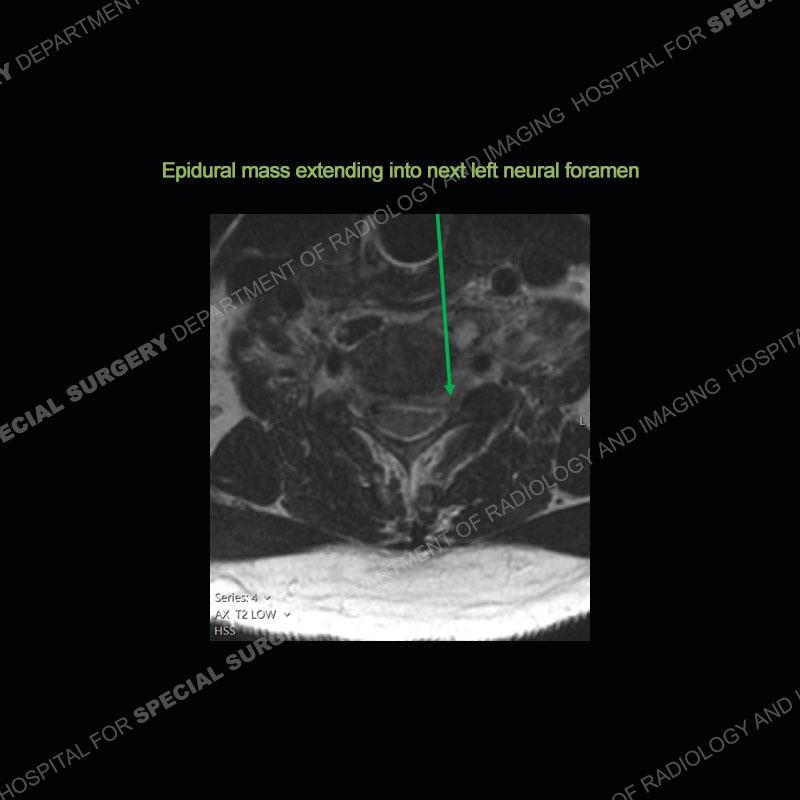

The radiographs demonstrate a prevertebral soft tissue fullness centered at C5-C6 that persists even on extension. There is a slight loss of disc height at C5-C6. The CT more readily shows the prevertebral soft tissue swelling at C5C6 where there is a punctate focus of gas. On the MRI, there is a marked amount of edema and a heterogeneous collection in the prevertebral soft tissue at C5-C6. Edema is present of the C5 and C6 vertebral bodies with a loss of the normal architecture about the disc space. A heterogeneous epidural collection has formed that causes compression of the spinal cord asymmetric to the left side and also precipitates severe left sided neural foraminal stenosis.